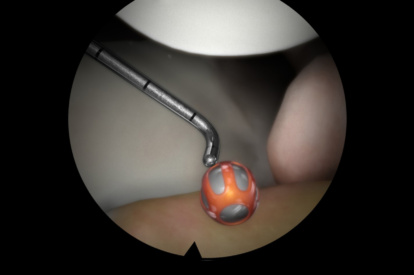

ARTHRO Mentor is an effective tool for arthroscopic surgery skills acquisition. With over 15 years of validation studies, it offers a line of simulated procedures, covering the 3 major joints (shoulder, knee, and hip) combining physical anatomical models with 3D images and dynamic haptic sensation, to allow users to learn key aspects of the procedures while providing tissue sensation.

- Adaptive tactile sensation on drilling, suturing, and shaving

- A library of modules with 80+ tasks, cases, and didactics